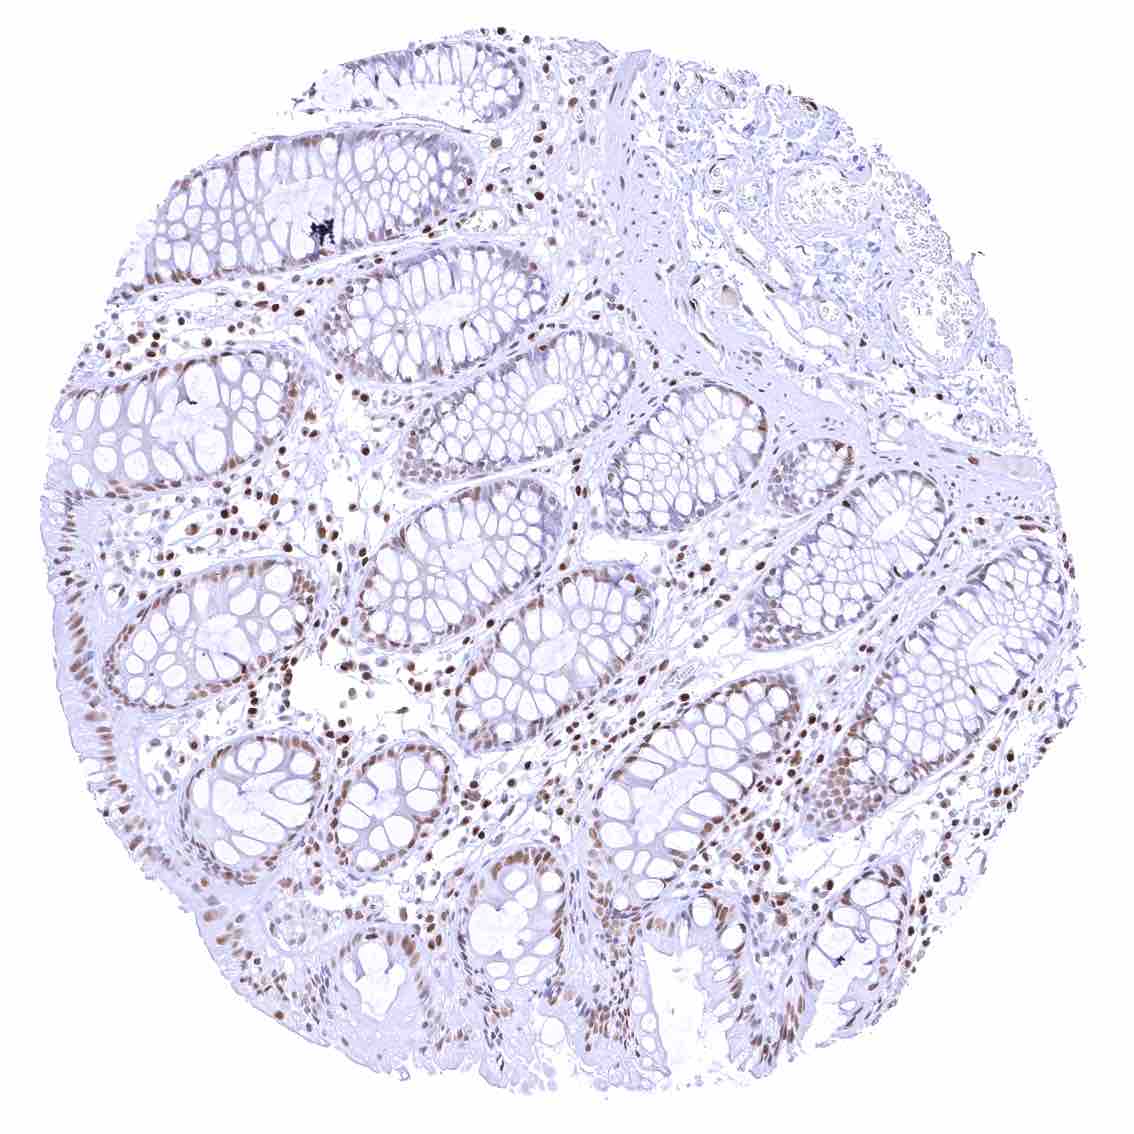

Rectum, mucosa